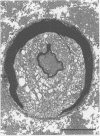

A patient with fulminant Guillain-Barré syndrome developed pupillary denervation, loss of all brain stem reflexes and a complete flaccid quadriparesis. Pathological studies confirmed this was due to a primarily demyelinating process and not an axonal form of Guillain-Barré syndrome.